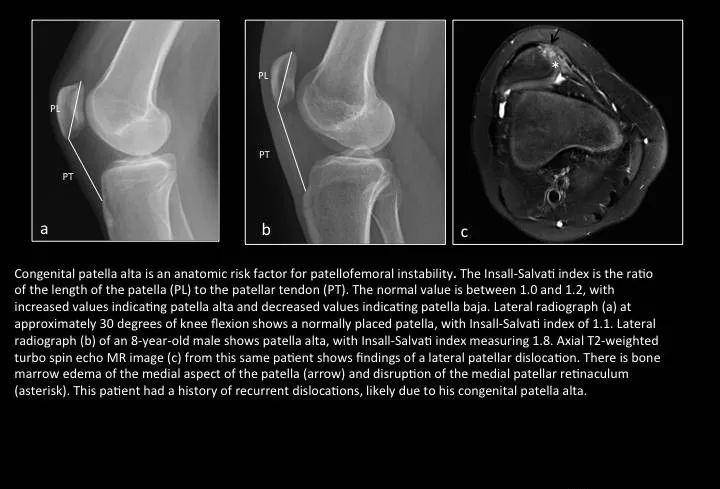

Fig. 7: Patella alta

图7:高位髌骨

a图正常位置髌骨,髌韧带长度(PT)/髌骨长度(PL)正常比值为1.0-1.2(国内文献一般小于0.8提示低位髌骨,大于1.2提示高位髌骨);b图PT/PL比值为1.8;c图示髌骨脱位状态,局部骨髓水肿。

高位髌骨通常无症状,尽管它是膝关节不稳定的重要解剖危险因素之一。